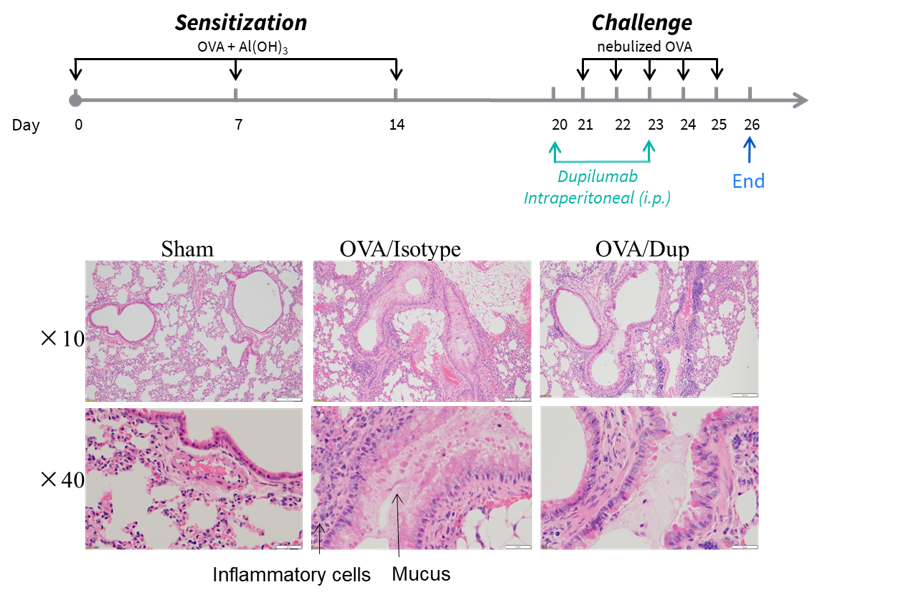

H&E staining of asthma-like model in B-hIL4/hIL4RA mice. Lung tissues were collected at the study endpoint. H&E staining results showed that the lung tissues from B-hIL4/hIL4RA mice exposed to PBS aerosols did not show any inflammation. OVA exposure resulted in a significant increase in peribronchial and perivascular inflammation in B-hIL4/hIL4RA mice. A significant reduction in eosinophils infiltration was observed in mice treated with dupilumab (in house).

Analysis of immune cells in BALF by FACS and IgE production in serum. BALF immune cells were isolated from B-hIL4/hIL4RA mice (n=4 or n=5). The number and proportion of eosinophils were analyzed by flow cytometry under the treatment of PBS/dupilumab (in house). After treatment of dupilumab (in house), the number of CD45+ cells and eosinophils were much lower than the positive control in homozygous B-hIL4/hIL4RA mice. Serum was collected at the study endpoint. IgE levels responded to OVA-specific antibody and total IgE levels were analyzed. The results show that the levels of IgE in mice treated with dupilumab (in house) is much lower than that in untreated mice.